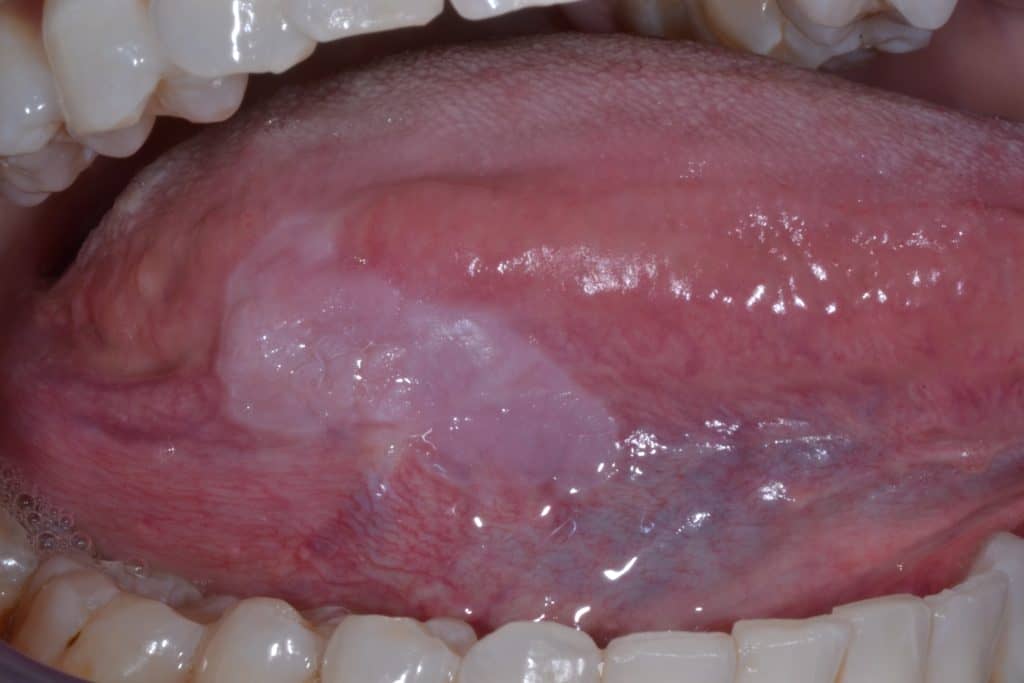

-لوکوپلاکیا (Leukoplakia) و اریتروپلاکیا (Erythroplakia)

-علائم: لوکوپلاکیا به صورت لکه یا پلاک سفیدرنگ است که با مالش پاک نمیشود. اریتروپلاکیا لکه قرمز مخملی شکل است. این ضایعات در زیر زبان و کف دهان بسیار خطرناک هستند. اریتروپلاکیا بالاترین پتانسیل تبدیل به سرطان (حدود ۹۰٪) را دارد.

-درمان: سرطان زیر زبان نیاز فوری به بیوپسی ضایعه دهان (نمونهبرداری) و بررسی آسیبشناسی دارد. درمان بسته به نتیجه پاتولوژی، از برداشتن کامل ضایعه تا پیگیری منظم و درمانی تهاجمیتر متغیر است.